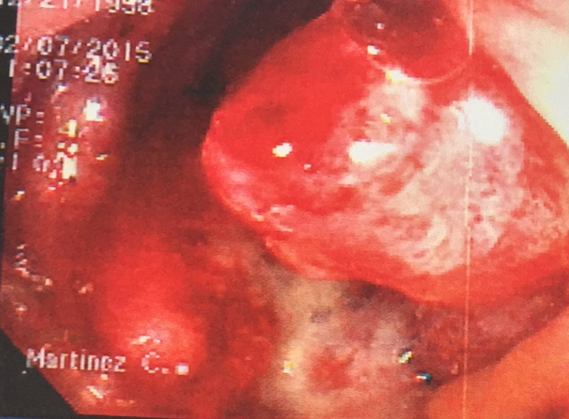

La colonoscopía es la herramienta que nos posibilita la adecuada detección, diagnóstico y pronóstico de padecimientos tales como el cáncer de colon.

Las pruebas diagnósticas que se emplean son mediante exámenes de laboratorio y gabinete: sangre oculta en heces, Colonoscopía (que consiste en la introducción de un tubo hueco iluminado, delgado y flexible, de un dedo de grosor, se utiliza para examinar el colon y tomar biopsias), Tomografía, Resonancia magnética (RMN)